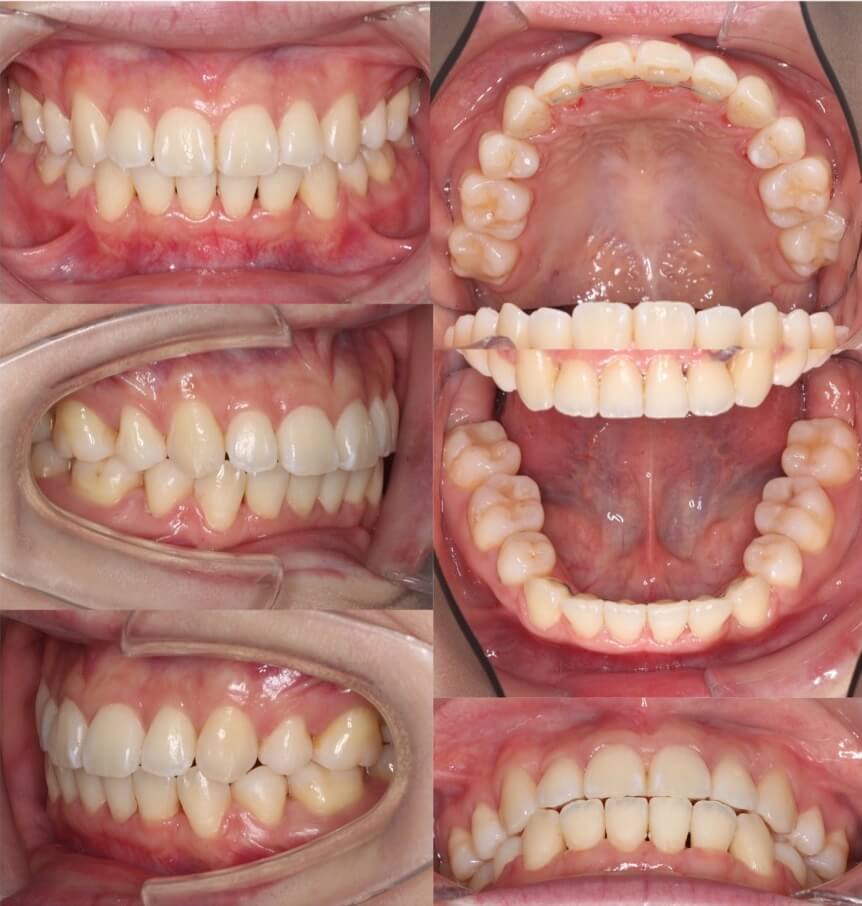

「男性は顔が引き締まる」

高校生男性・唇側矯正装置・下あご後退型

当初は、抜歯矯正治療にするかしないかで、治療方針に迷ったケースですが、最終的には患者さんの希望に沿って抜歯矯正治療にしました。歯の動きがゆっくりであったため、治療期間が3年を超えてしまいました。

<症例概要> 難易度:★★★★☆

主訴:口元の突出・前歯のガタツキ

年齢・性別:高校生男性

住まい:千葉県八千代市市

症状:下顎後退・叢生

治療方針:抜歯空隙の閉鎖(最大固定)

治療装置:唇側矯正装置

固定:歯科矯正用アンカースクリュー(頬側x2)

抜歯:上下第一小臼歯(計4本)

治療期間:3年4か月

リテーナー:上下プレートタイプ+フィックスタイプ

治療費用:968,000(税込)

代表的副作用:痛み・治療後の後戻り・歯根吸収・歯髄壊死・歯肉退縮